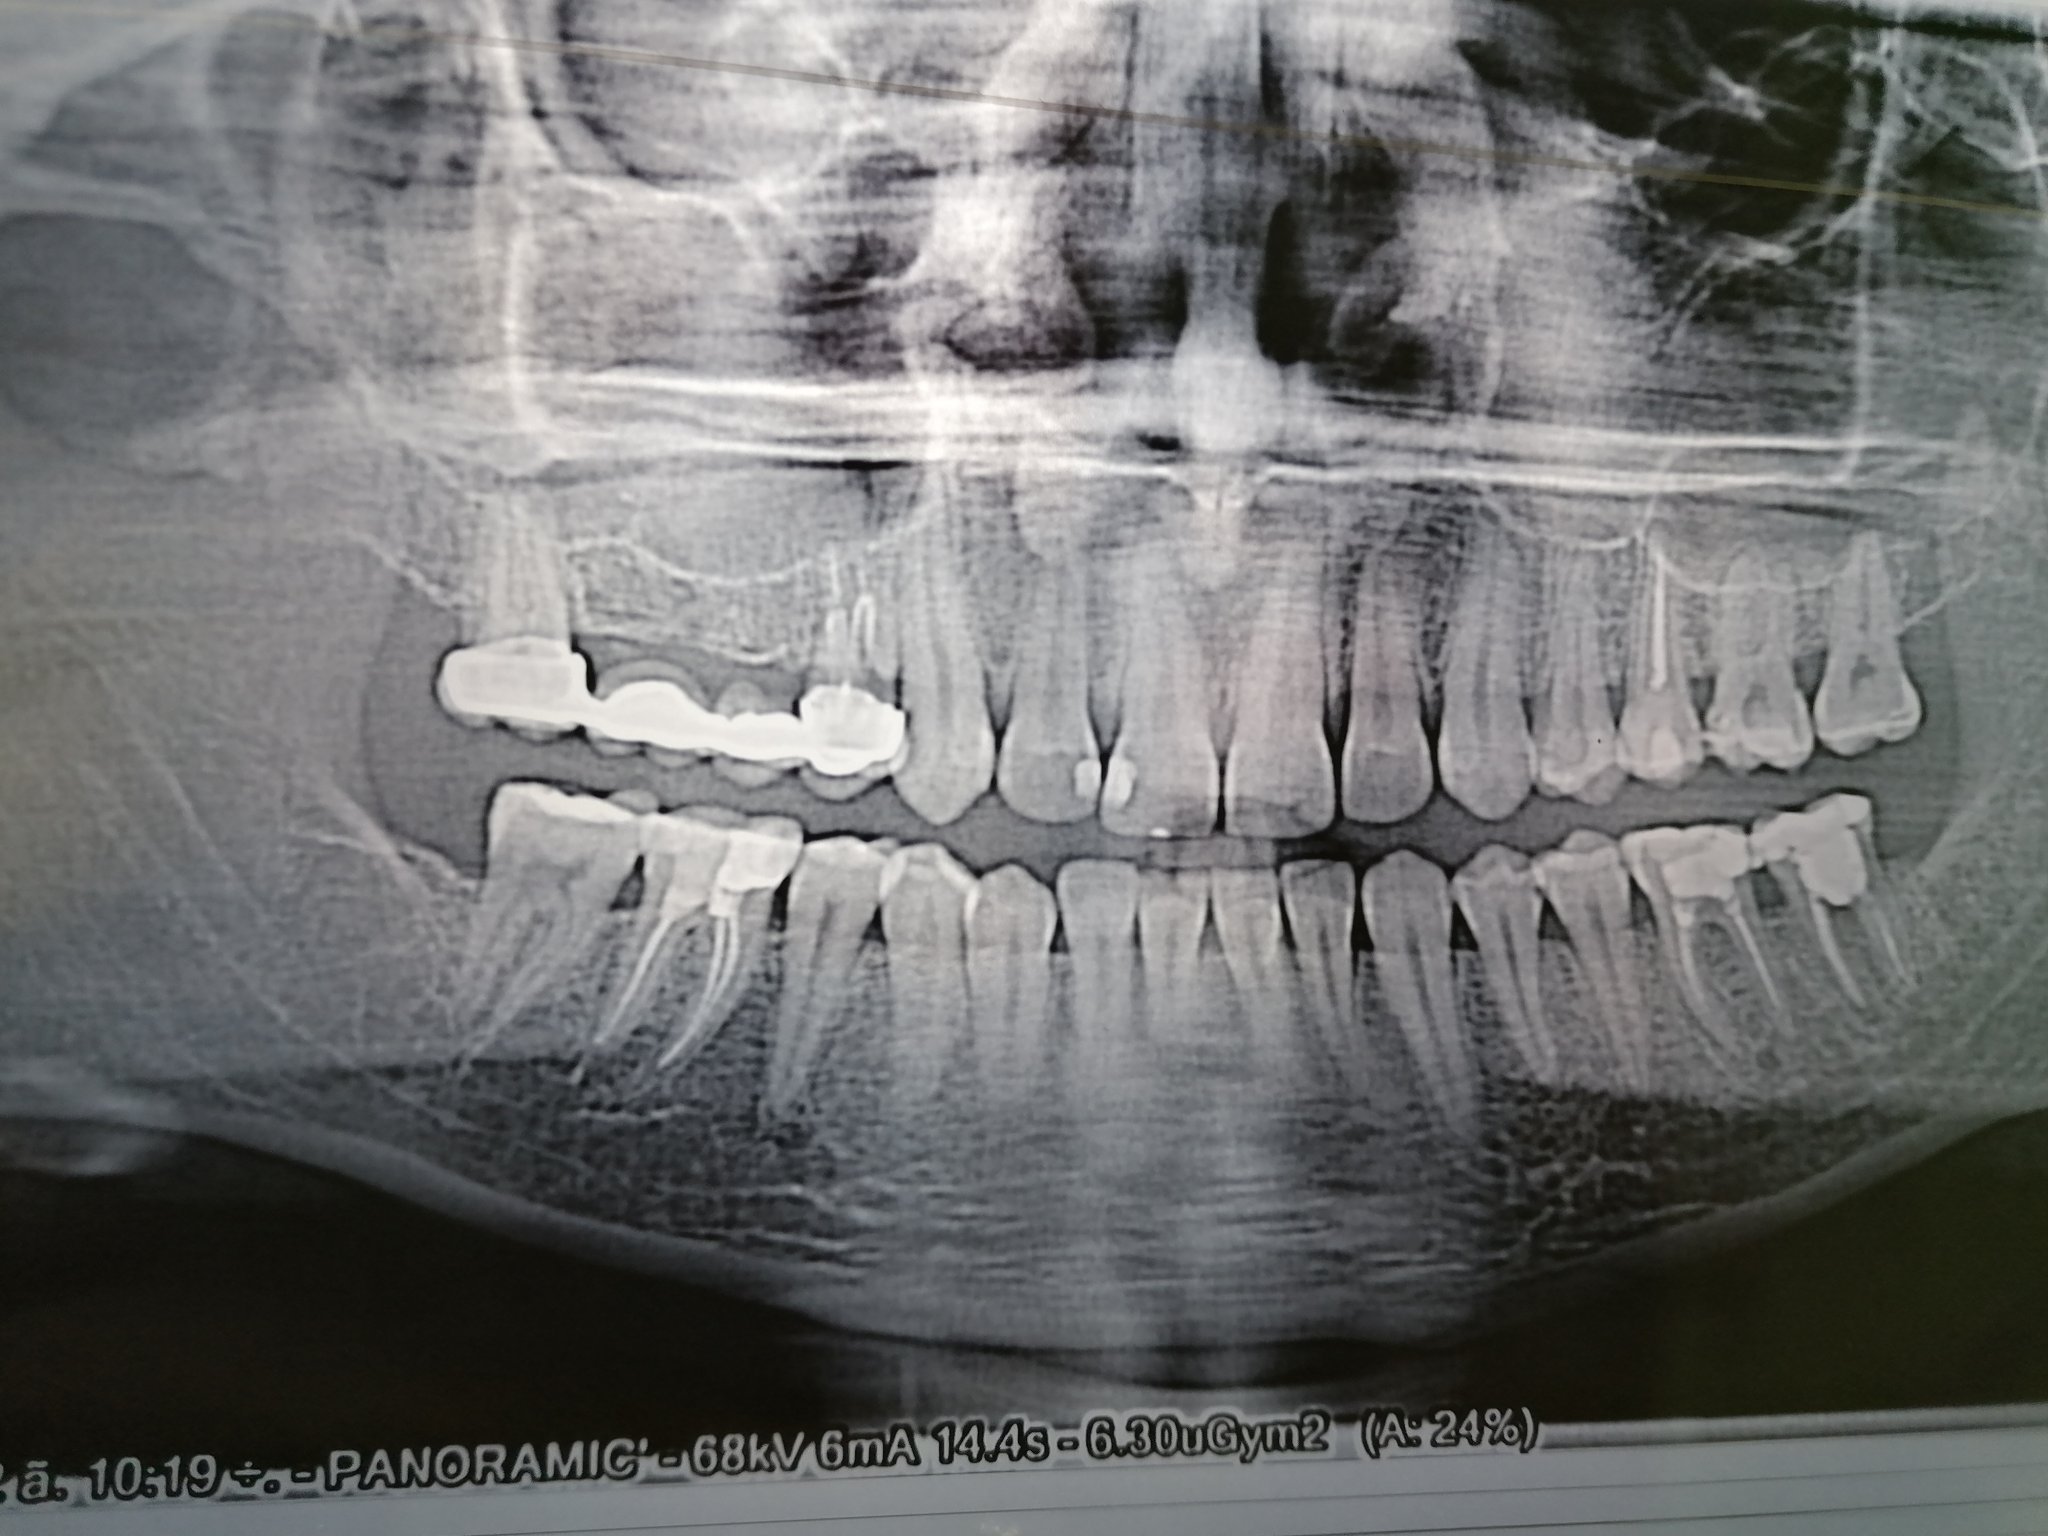

Здравейте! Някой може ли да ми каже дали имам проблем с този мост, защото нещо ми е възпален венеца около него. Според моята зъболекарка няма нищо. Имам и проблем с 7 ми зъб долу в ляво. Сутрин като стана ме боли,а уж е мъртва. Благодаря

=600 height=354]//cdn.bg-mamma.com/pdHd/QnxrI.jpg[/img]

Здравейте, преди известно време ми беше проведено кореново лечение на 5 зъб, който сега ме наболява леко- тъпа болка. Направих сегментна снимка, имам чувството, че каналът не е запълнен достатъчно добре, но не съм компетентно лице. Някой би ли могъл да помогне с мнение? Също така, на съседния четвърти, има малко затъмняване между него и 5, ако случайно се вижда кариозен процес, въпреки че като е малко едва ли е видимо. Благодаря Ви.

architectgirl, зъбът не е добре запълнен, включително има и хроничен възпалителен процес около корена на зъба. Трябва да се проведе отново кореново лечение на този зъб.

Когато се свали пломбата на петия зъб ще може да се огледа най-добре четвъртия и да се прецени какво е неговото състояние около пломбата.